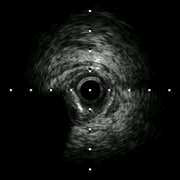

过程(2): 送IVUS导管至前降支近中段,回撤评估左主干-前降支病变情况。左主干末端MLA 2.58mm2,斑块负荷87%。

![]()